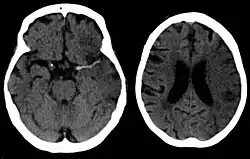

A CT showing early signs of a middle cerebral artery stroke with loss of definition of the gyri and grey white boundary

Dense artery sign in a patient with middle cerebral artery infarction shown on the left. Right image after 7 hours.

CT scans may not detect ischemic stroke, especially if it is small, of recent onset,[10] or in the brainstem or cerebellum areas (posterior circulation infarct). MRI is better at detecting a posterior circulation infarct with diffusion-weighted imaging.[79] A CT scan is used more to rule out certain stroke mimics and detect bleeding.[10] The presence of leptomeningeal collateral circulation in the brain is associated with better clinical outcomes after recanalization treatment.[80] Cerebrovascular reserve capacity is another factor that affects stroke outcome – it is the amount of increase in cerebral blood flow after a purposeful stimulation of blood flow by the physician, such as by giving inhaled carbon dioxide or intravenous acetazolamide. The increase in blood flow can be measured by PET scan or transcranial doppler sonography.[81] However, in people with obstruction of the internal carotid artery of one side, the presence of leptomeningeal collateral circulation is associated with reduced cerebral reserve capacity.[82]